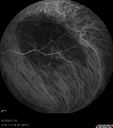

FLUORESCEIN ANGIOGRAPHY: Fluorescein angiography of the left eye shows early hypofluorescence and hyperfluorescence around the area of the choroidal mass in the left eye with filling of what looks to be its own vasculature. In the later frames of the angiogram, there is a rim of hypofluorescence around it, where there is mottled pigment and then some hyperfluorescence within the lesion. The lesion does appear to have two components, one of which is a circular area in the center and then a more diffuse area around the periphery.

The right eye shows a normal fill with no evidence of any macular lesions.